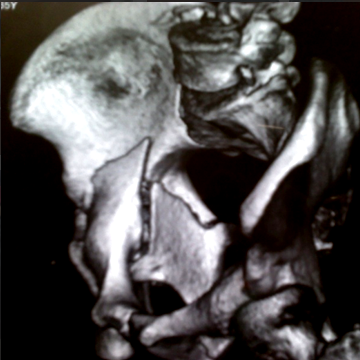

Complex Trauma Care

Specialized treatment for severe fractures and injuries to restore function and mobility.